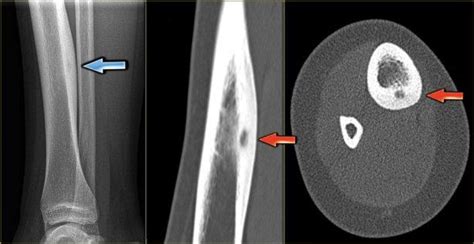

Остеоид остеома кости: причины, симптомы, лечение